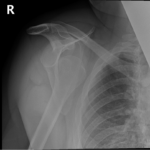

- Shoulder Fractures.

- Clavicle Fractures.